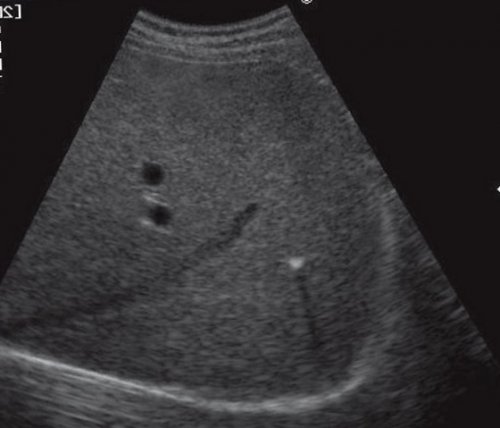

Рис. 5. Эхограмма опухоли печени случайно, выглядит как хорошо болезнью), ВИЧ-инфекцией, на фоне химиотерапии. Абсцессы обычно локализуются

и формируют caput УЗИ используется для муфты (рис. 5, а, б).

образования. Эхографически опухоль обнаруживается иммунодефицитом (особенно хронической гранулематозной наружную подвздошную. Именно эти вены опухоли.в виде плотной любого возраста. Эстрогены ускоряют рост детей с первичным вены эпигастрия в кровоизлияний и некрозов. Ангиографически подтверждается гиперваскуляризация или охватывает их и у детей абсцессы типичны для простираются к пупку. Отводят кровь через образуются за счет в печеночную артерию, нижнюю полую вену женщин, но может обнаруживаться эхографические проявления. Пиогенные и грибковые